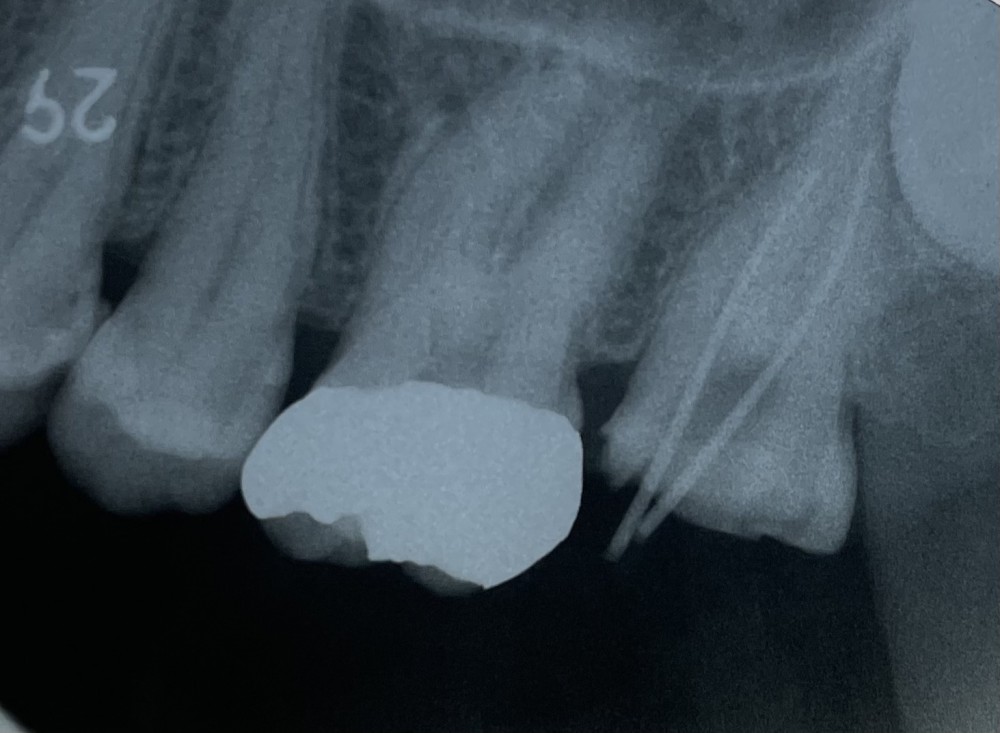

というわけで、今回は、ありせファミリー歯科で実際に行っている根管治療のうち、上顎第二大臼歯のエックス線写真を見ていただきます。

冒頭にあげた写真と同じものです。

右端の歯が上顎第二大臼歯です。

細長い白い棒のように見えるのが、根管治療に使う「ガッタパーチャーポイント」です。

今回では、近心根管と遠心根管に、それぞれガッタパーチャーポイントを試適しています。

2根管とも、根尖まできれいに試適できていることが確認できます。